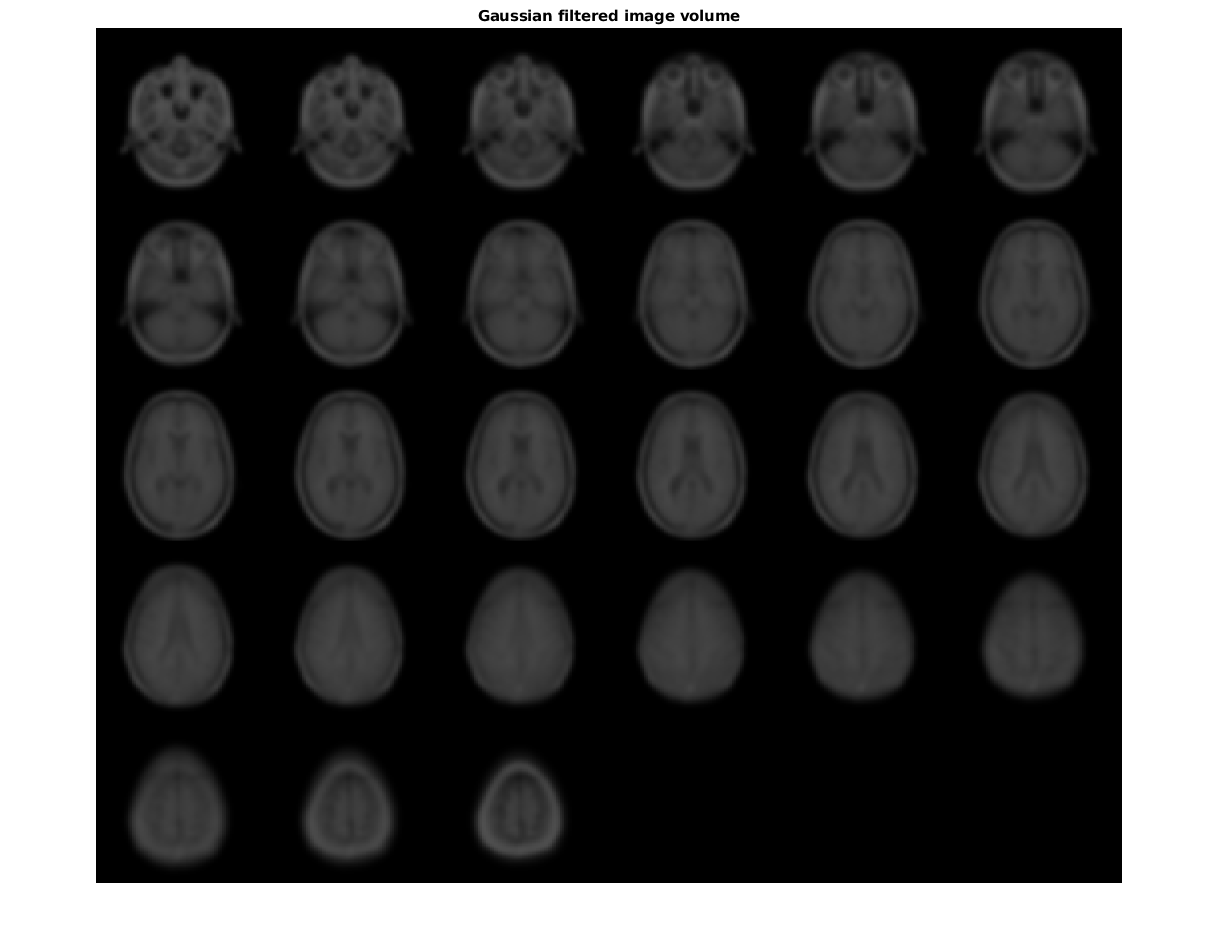

Сглаживайте изображение с помощью 3-D Гауссова фильтра.

siz = vol.siz;

vol = squeeze(vol.D);

sigma = 2;

volSmooth = imgaussfilt3(vol, sigma);

figure

montage(reshape(volSmooth,siz(1),siz(2),1,siz(3)))

title('Gaussian filtered image volume')

Figure contains an axes. The axes with title Gaussian filtered image volume contains an object of type image.